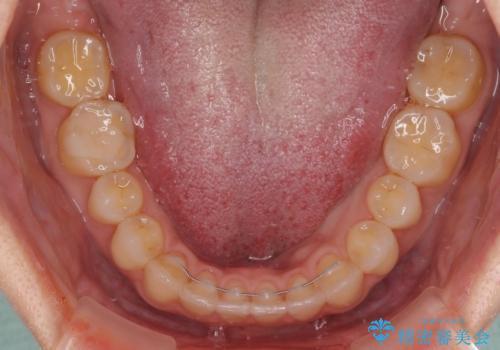

【モニター】狭い上顎歯列とオープンバイト 急速拡大装置を用いた矯正治療

- 前歯の開咬を気にして来院された患者様です。

上顎歯列が狭窄していたため、急速拡大装置により上顎骨を側方に拡大し、その後インビザラインにて矯正治療を行うこととしました。

舌の突出癖が開咬の原因であったので、改善のための舌トレーニングを行っていただきました。

舌トレーニングは後戻りにも大きく影響するため、とても重要なトレーニングです。